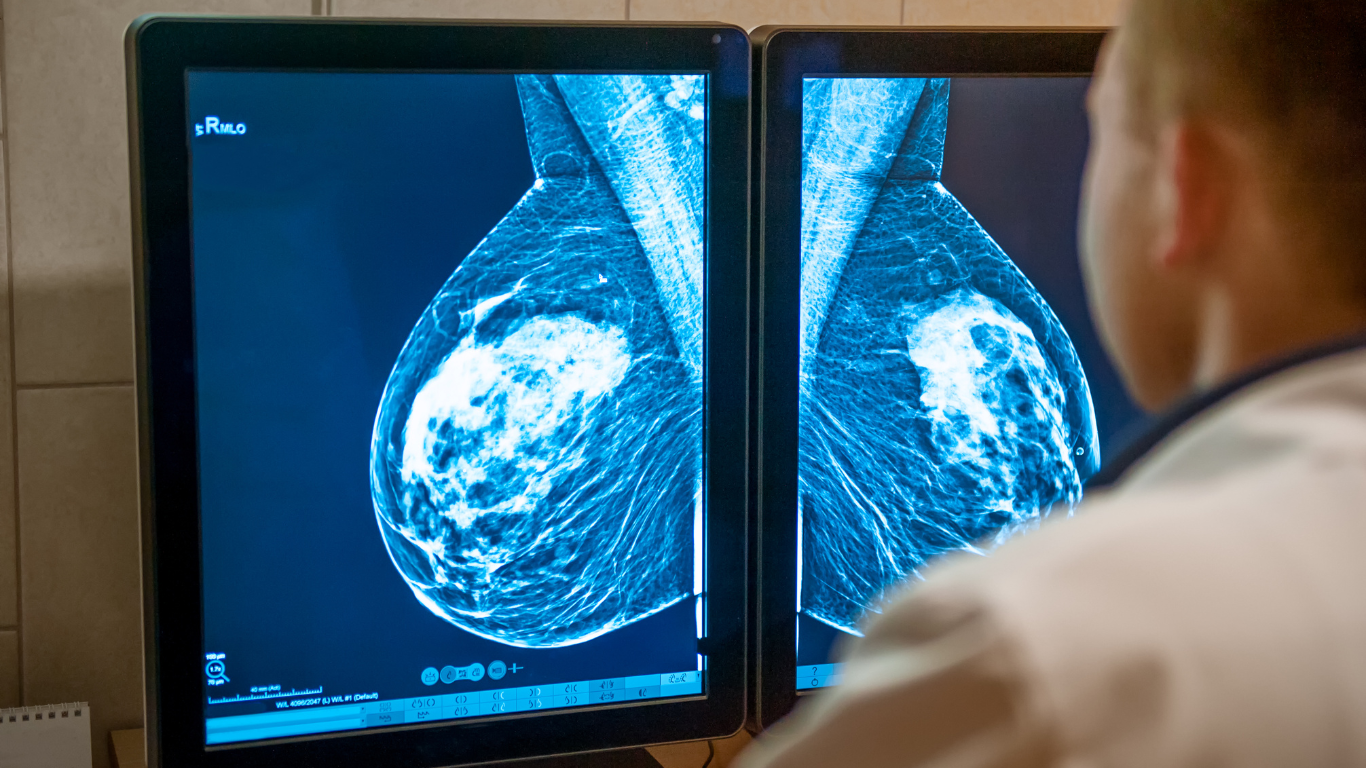

Médico observa una mamografía con tecnología de nanotecnología

El cáncer de mama triple negativo (CMTN) es una de las formas más agresivas y difíciles de tratar del cáncer de mama. A pesar de los avances en las terapias tradicionales, el tratamiento de este tipo de cáncer sigue siendo un desafío. Sin embargo, investigaciones innovadoras están abriendo nuevas puertas para mejorar el tratamiento del CMTN, utilizando la nanotecnología como herramienta clave para potenciar la respuesta inmunitaria a los tratamientos convencionales.